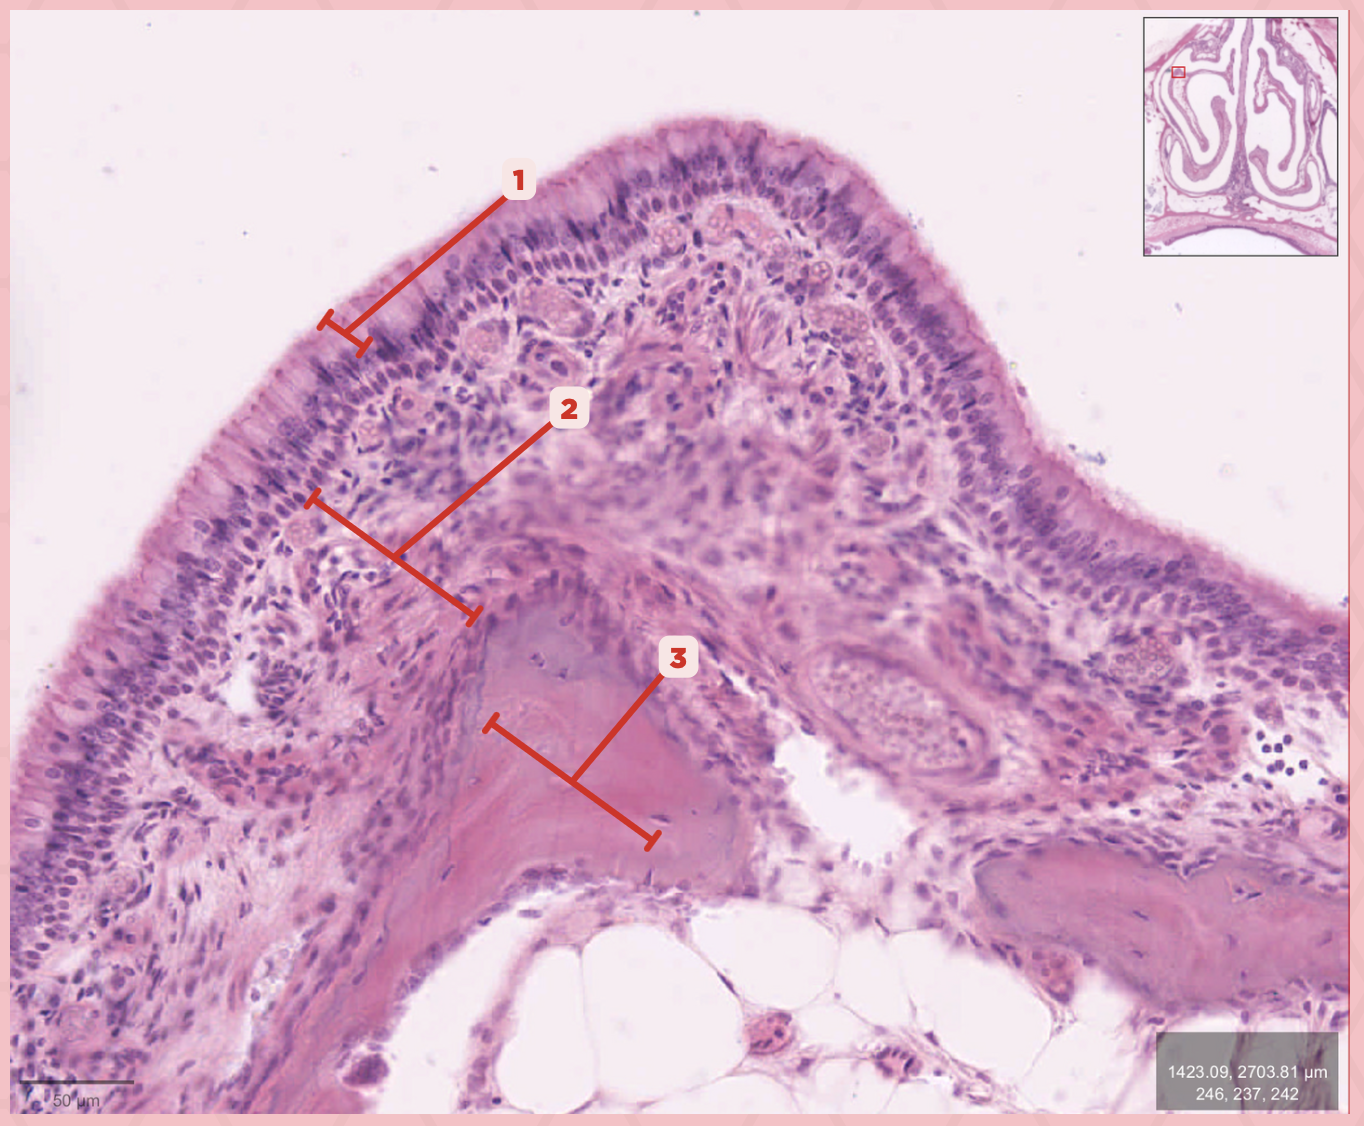

Respiratory Epithelium

Identify the structure labeled as 1.

Lamina Propria

Identify the structure labeled as 2.

Bony spicule

Identify the structure labeled as 3.

Respiratory Epithelium

What epithelium lines this structure?

Ciliated pseudostratified epithelium

What type of epithelium lines this structure?

Respiratory Epithelium

Identify the structure labeled as 1.

Mucosa

Identify the structure labeled as 2.

Bone

Identify the structure labeled as 3.

Keratinized stratified squamous epithelium

What’s the lining epithelium at #3?

No

Are Glands present at #1?

Lamina Propria

Identify the structure labeled as 1.

Adipocytes

Identify the structure labeled as 2.

Keratinized stratified squamous epithelium

Identify the structure labeled as 3.